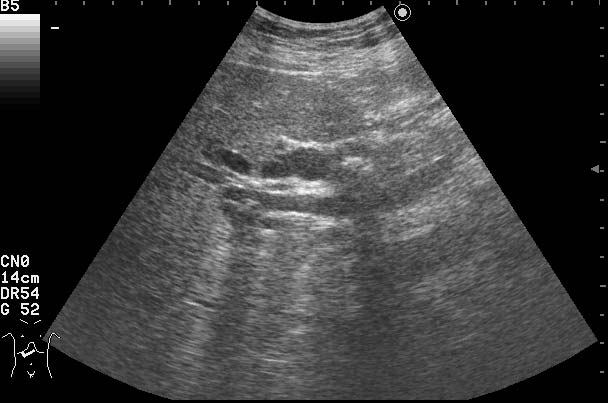

Женщина 70-ти лет с бессимптомной желтухой.

Сонограммы холедоха:

На верхнем снимке можно предположить внутрипросветную опухоль в холедохе.

В сущности, ответ правильный уже был - это опухоль холедоха с инкрустацией ее ткани.

Благодаря такой необычной презентации опухоль была ошибочно принята за камень холедоха.

Спасибо!Очень интересный случай,смотрю уже который раз.Можно ошибиться,но "камень"обволочен мягкотканной структурой-гипоэхогеной,раздвигая стенки коледоха,типа "веретено".Так,что коллега права-опухоль